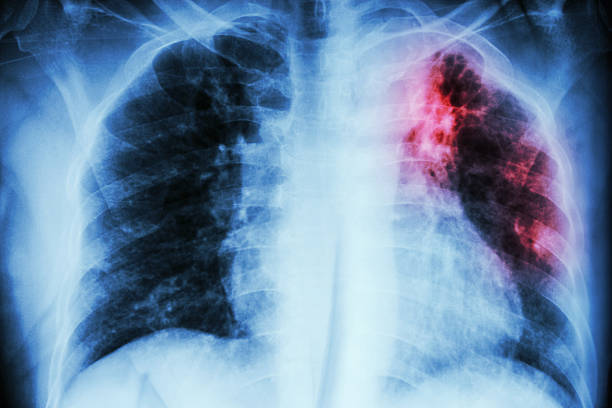

폐 질환과 구분하기 위해서는 X-RAY, 혈액검사 이외에도 객담검사, 흉부 CT를 추가로 시행하게 됩니다.

흉부 엑스레이는 결핵 검사 진단 방법 중 하나지만 단독으로 진단하지는 않으며, 흉부 엑스레이 검사 상 결핵이 의심된다면 확진 판정을 위해 혈액 검사 및 객담검사를 추가로 실시합니다.